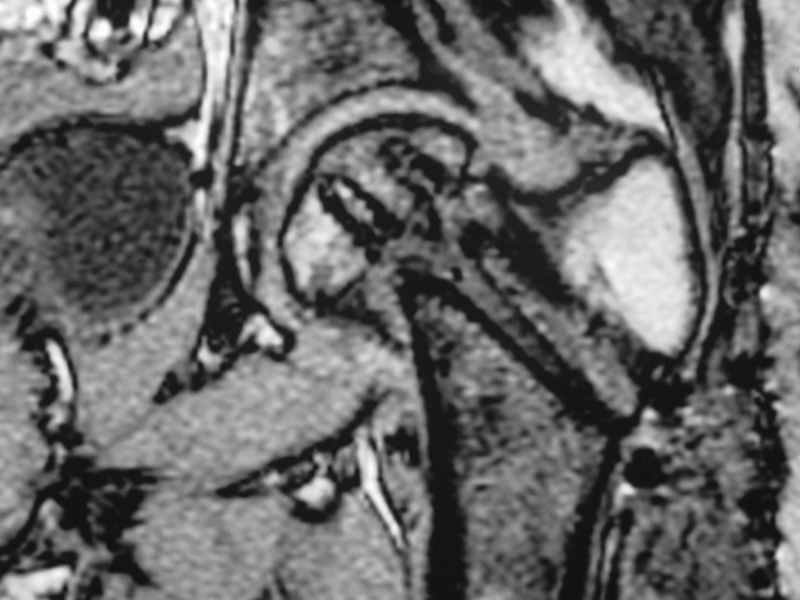

Erden K?l?c 16 Октябрь 2005, 00:03

I would leave it as it is. Because surgical intervention will not be able to prevent osteonecrosis if it is going to be. MRI may be helpful to determine union if there is any and also gives an idea about the viability of the head.

Erden K?l?c, MD

Gulhane Military Medical Academy